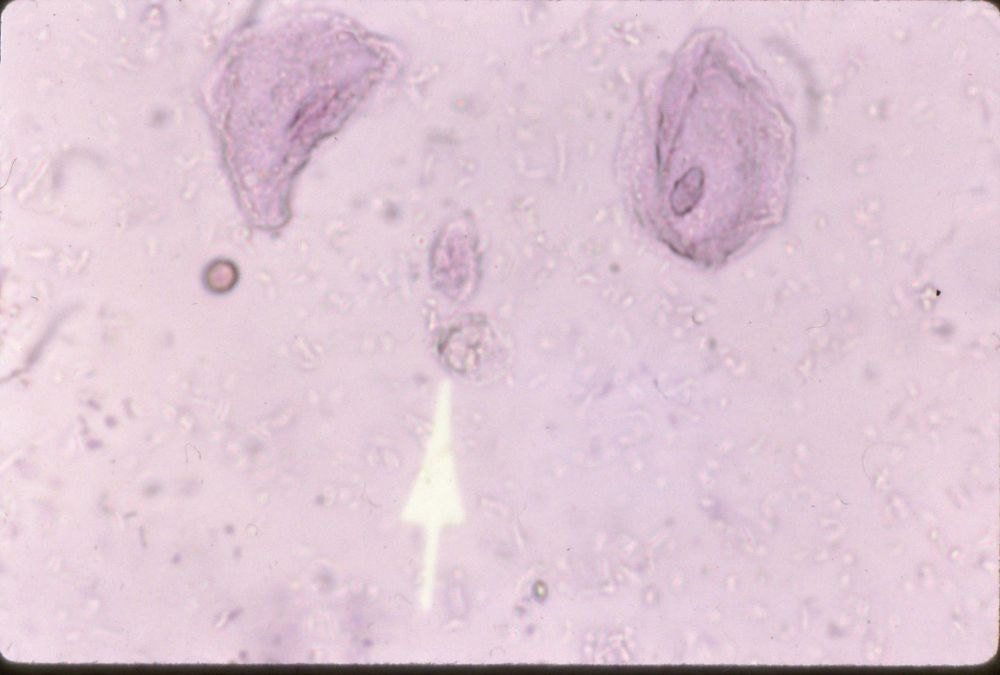

Image:

Artifact Sec (image/jpeg)

Artifact and SEC |